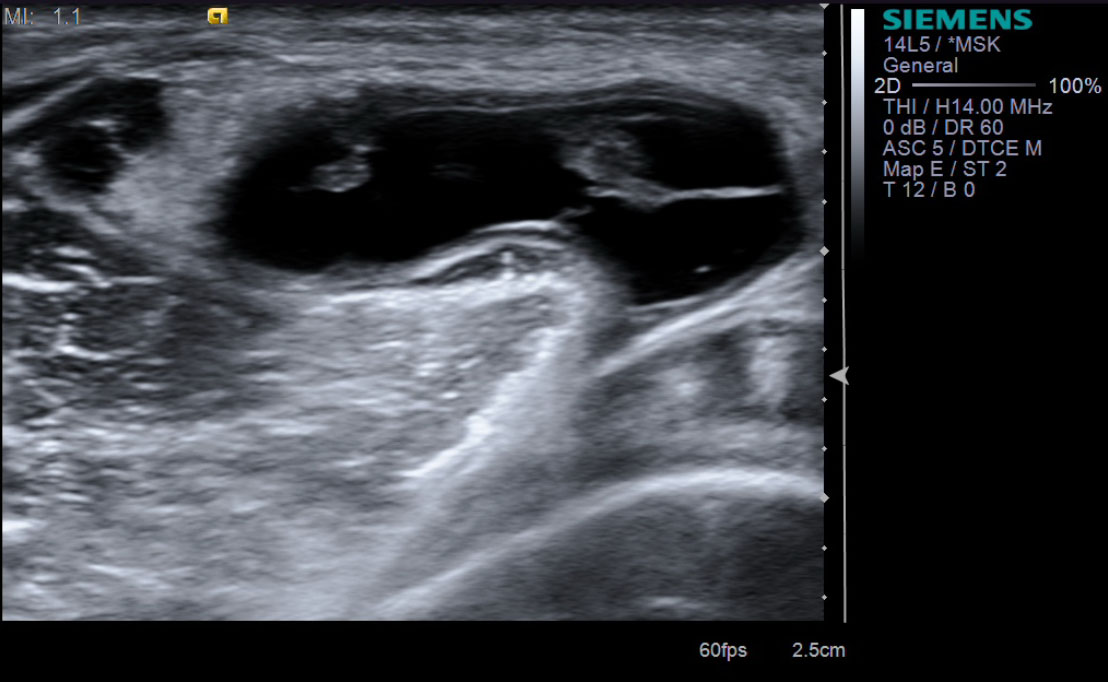

14. Take sonographic images documenting the reduction in size of the Baker's cyst.

description